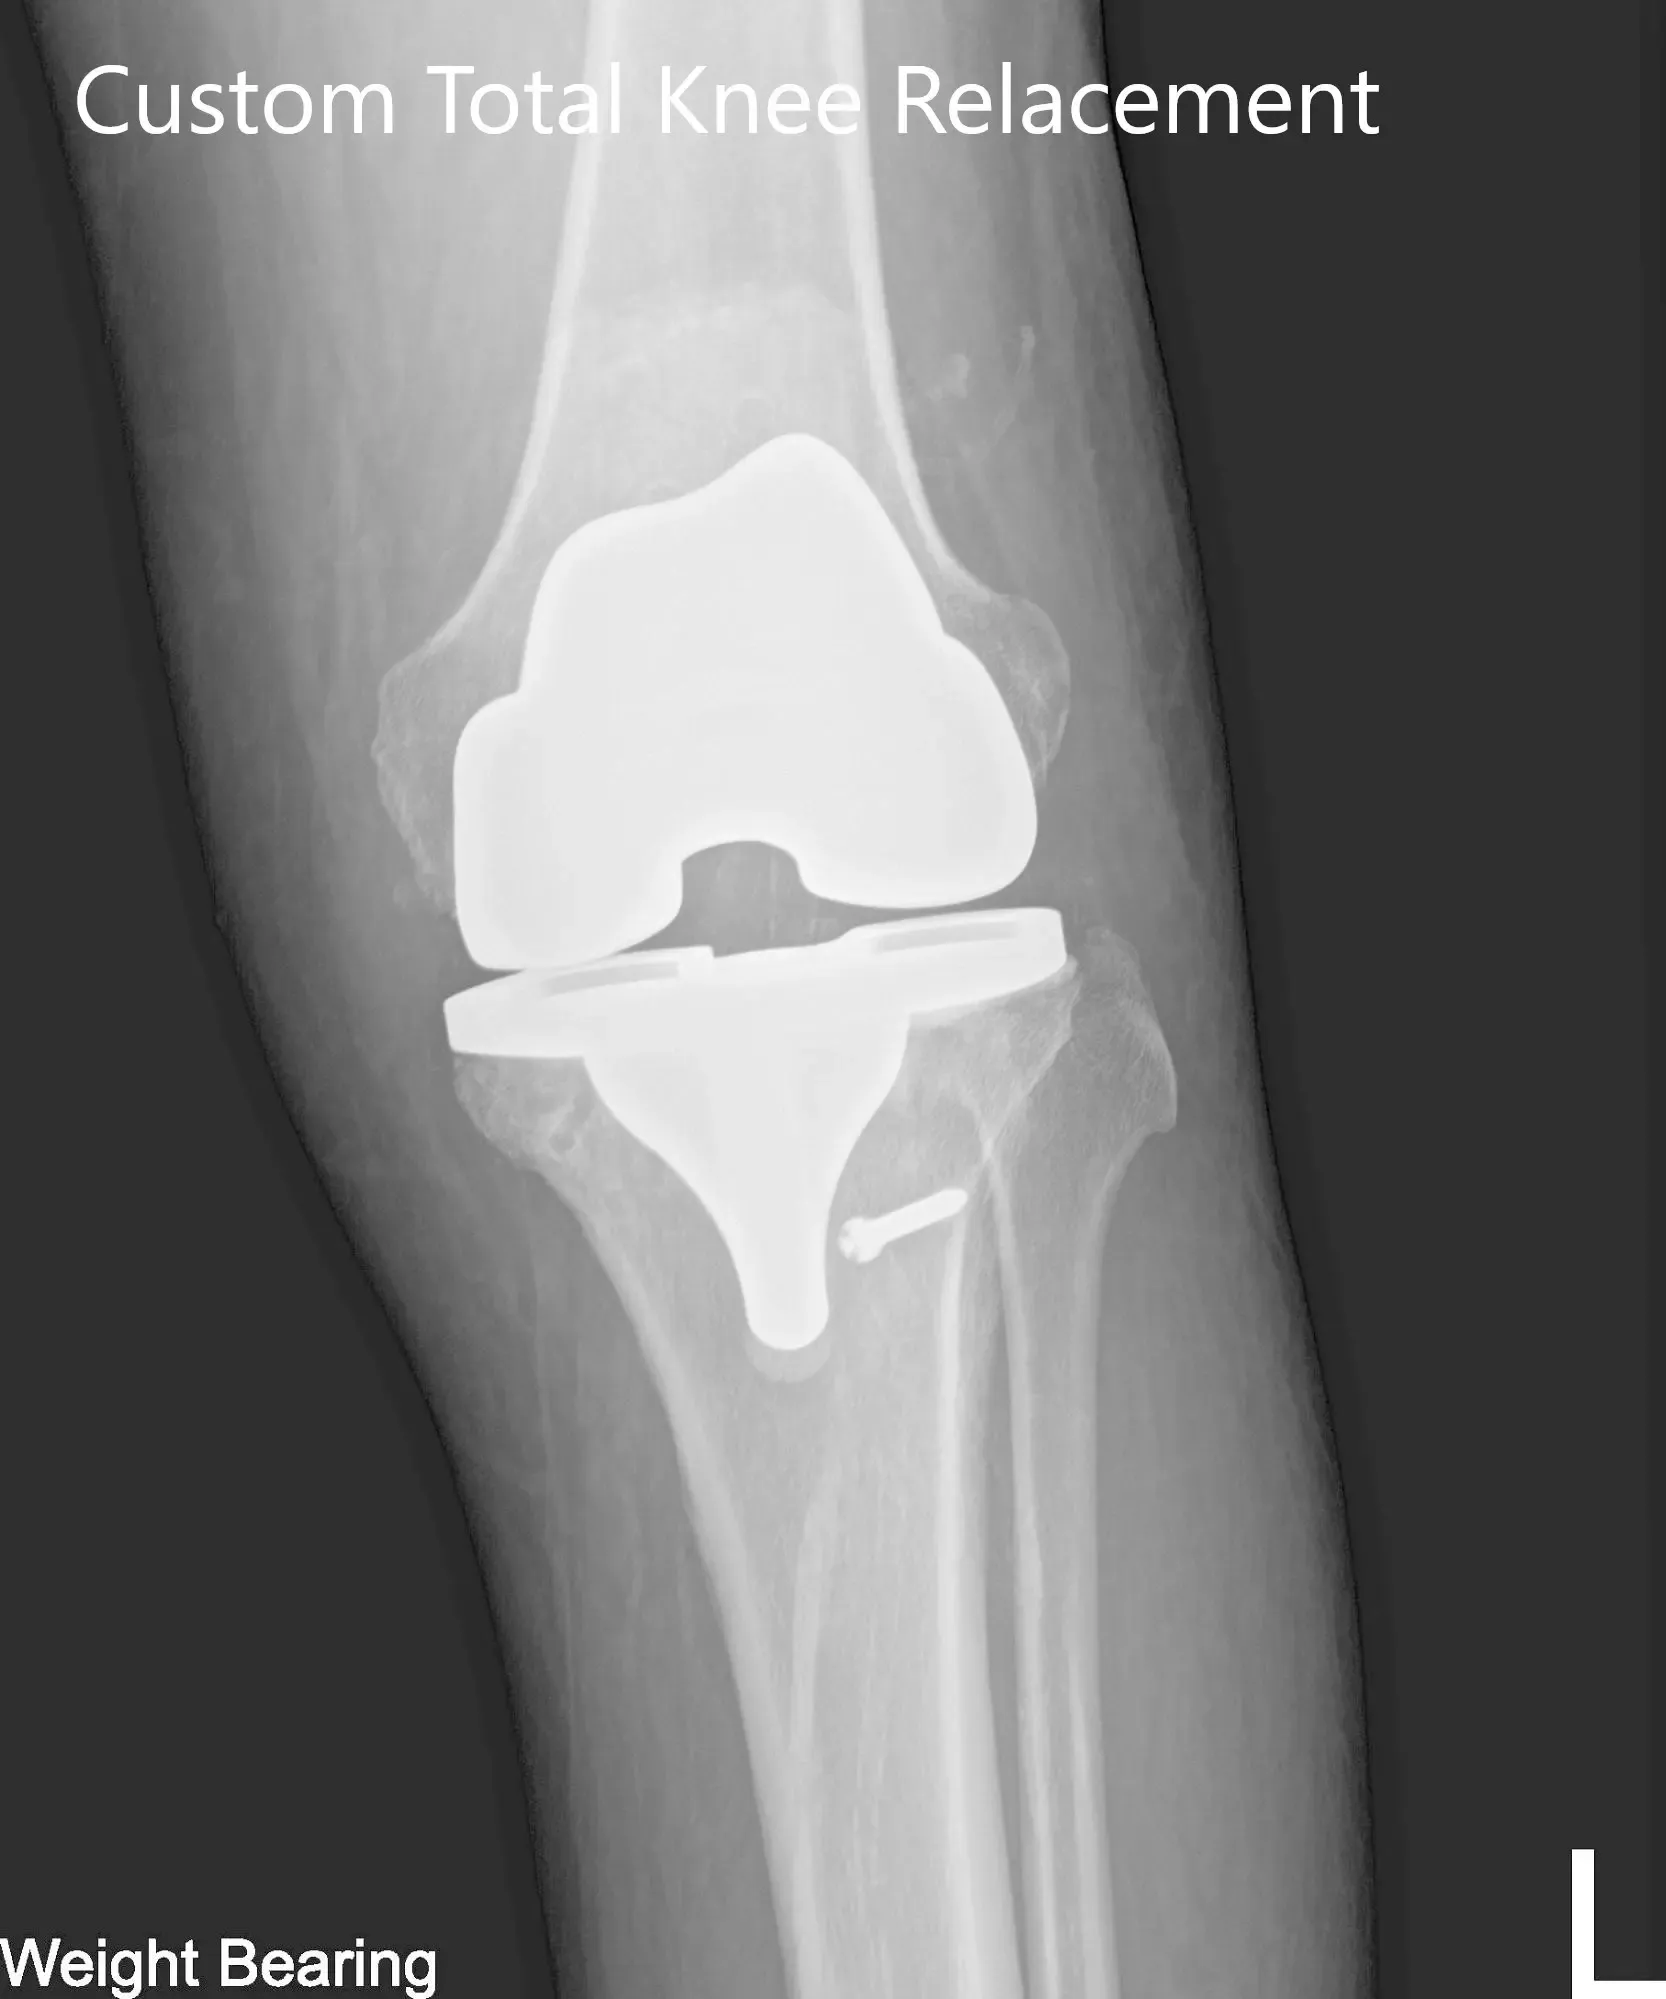

El paciente se sometió a una tomografía computarizada preoperatoria unas semanas antes de la cirugía. Los datos se utilizaron para crear instrumentos impresos en 3D personalizados e implantes únicos específicos para cada paciente. Los datos se utilizaron para crear un plan preoperatorio que detallaba cortes óseos y desplazamientos femorales. Los implantes personalizados aseguran que se preserve la mayor cantidad posible de hueso y que se recree la biomecánica biológica.

Implante – Artroplastia total de rodilla izquierda usando fémur personalizado, tibia, rótula y polietileno de 6 mm personalizados

Radiografía postoperatoria de la rodilla izquierda que mostró visión AP y lateral